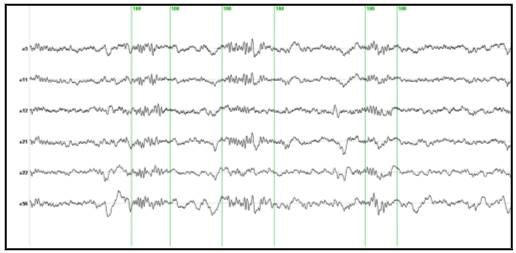

Figure 4 shows some original EEG traces for a segment where three spindles were identified. The vertical markers indicate the timing of the spindles as detected from their spectral envelope. Figure 5 (lower panel) shows the modulus of the MaSTiF decomposition, d(t,w), for the EEG segment shown in Figure 4 and its associated simplicity test map (Figure 5, upper panel). The simplicity map indicates the time frequency points where the map seems to be produced by a simple generator configuration, i.e., all sensors have approximately the same phase for the given time-frequency pair.

Figure 4. Original EEG traces with markers (green vertical lines) indicating the spindles identified from the spectral envelope.

The results of Figure 5 indicate the presence of the several time-frequency energy spots (see lower panel). In particular, the three spindles shown in Figure 4 are clearly delineated as strong time frequency energy peaks at 3.6, 6.8 and 11 secs. Interestingly, the plot indicates the simultaneity of 12 and 14 Hz spindles in nearly all cases. This is suggestive of the coexistence of different neural processes within a single spindle. The evidence that these are in fact different neural processes that coexist in time is given by the differences in topography of the simultaneous spindles at 12 and 14 Hz shown in Figure 6. This plot presents an expanded view of the middle spindle occurring between 6 and 8 secs. This spindle is selected because the simplicity plot suggests the existence of simple maps for both frequencies, i.e., 12 and 14 Hz. Importantly, while the existence of different scalp maps is a certain evidence of difference in neural generators, the opposite does not hold. Similar scalp maps can be produced by different configuration of generators due to the existence of silent sources, i.e., sources that produce no scalp EEG (e.g. closed fields). In fact this is the origin of the non-uniqueness of the neuroelectromagnetic inverse problem.